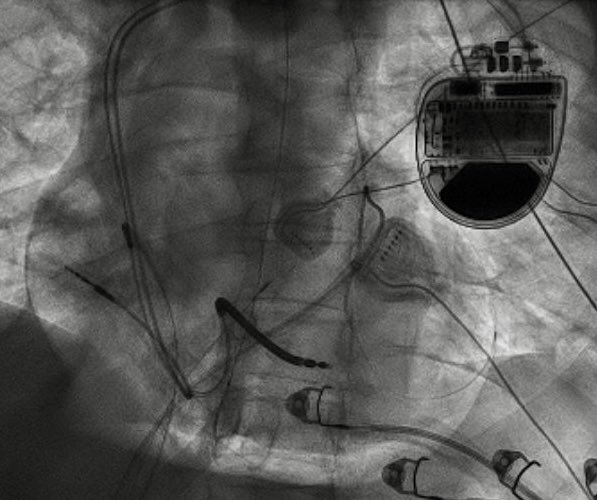

Question for EP fellows: Elderly M with dual ICD.

Incidental or Iatrogenic VF? What programming feature is shown here? How do you fix? #Epeeps @EvanBlankMD @FaisalMMerchant @melchami99 @narrowQRS @rdschaller

@naijaQRS @FaisalMMerchant @melchami99 @narrowQRS @rdschaller Looks like a short long short sequence with MVP. There’s probably a more elegant solution but could just make it DDD.